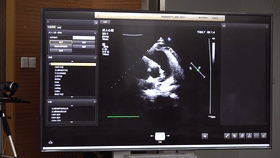

5G遠程會診現場,西安國際醫學中心心內科張衛澤主任、超聲科陳姍姍主任打開4K高清顯示器,屏幕上立刻出現了商洛國際醫學中心的B超畫面,一位醫生正在為患者做心臟B超,隨著探頭的轉動,超聲機器上的畫面清晰可見,雖然兩家醫院相距一百多公里,但畫面流暢,沒一點拖沓。